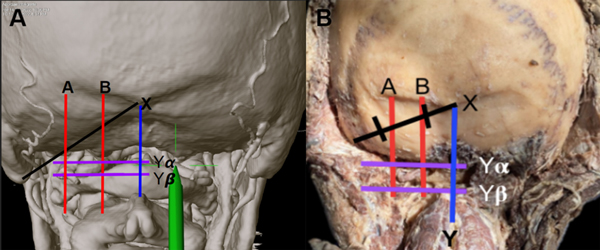

Se definió el segmento de riesgo de la Arteria Vertebral a la porción horizontal del sV3-AV que fue delimitada por 2 líneas verticales definidas previamente por Arnautović KI et al22: Línea A: En la entrada de la arteria al surco del arco posterior del atlas. Línea B: En la unión del borde medial de la faceta del atlas y la arteria, justo antes de su entrada al compartimiento intradural (Fig.2).

Figura 2. Ilustración de los reparos utilizados para realizar las mediciones en una ATC (A) y en un preparado cadavérico (B).

Se trazó una línea entre el Inion y la punta de la mastoides (línea X), que dividimos en tres tercios. Se buscó una correlación entre el sV3-AV y el tercio medio de dicha línea. Se consideró que la arteria estaba dentro del tercio medio de dicha línea si estaba presente en un porcentaje mayor o igual al 70%.

Luego se midió la distancia en el plano cefalocaudal desde el inion a los bordes del sV3-AV, para determinar su ubicación en este plano (Línea Y (borde superior), Y (borde inferior). (Fig. 2).